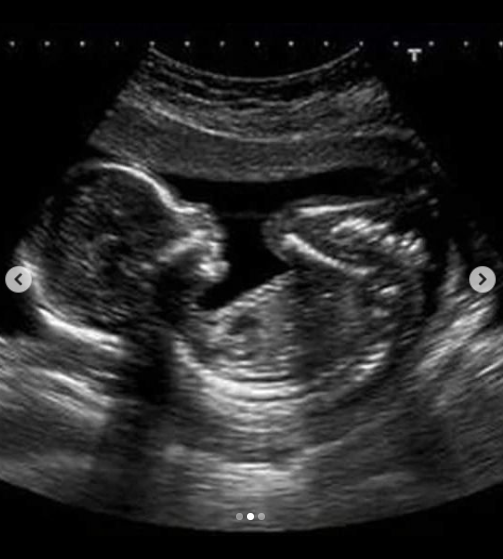

Женщина рассказала, что обратилась в больницу на 22-й неделе беременности с жалобами на тянущие боли внизу живота и кровянистые выделения. Ее положили в отделение патологии, где она прошла УЗИ.

"Сердцебиение было в норме, и также на второй день обследования сказали, что плод развивается хорошо, в свой срок. В тот же день к вечеру у меня начались боли внизу живота и поднялось давление. Я обратилась на акушерский пост к медсестре, на что они сказали сдать анализ мочи, но результаты были положительными. 10 декабря ближе к 5-6 утра у меня начались схватки, снова обратилась к медсестре с сильной болью, поскольку уже чувствовала, что головка ребенка выходит. В ответ от медсестры я услышала, что мне нужно потерпеть до 8 утра и дождаться прихода врача", — пишет казахстанка.

"Сказали, чтобы сама легла на каталку, тогда я чувствовала шевеление плода. Унесли меня, выяснилось, что не было свободных мест. Пока искали, прошло еще несколько минут. Здесь каждая минута дорога! Наконец-то нашли свободную палату. В 8:50 я родила своего ребенка, но уже мертвого — остановилось сердце. Ей можно было сохранить жизнь. Это был здоровый малыш, я чувствовала ее сердцебиение. Самое страшное, что после того, как я родила, врачи просто стояли и смотрели, ребенку даже не попытались сделать массаж сердца. Ее положили в мусорный желтый пакет, куда кидают обычно отходы," — поделилась женщина подробностями и приложила фотографию УЗИ.